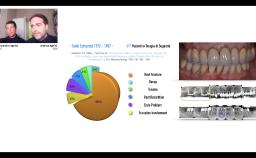

Clinical problems with implant restorations comprise biological and technical complications and are often associated with esthetic and/or functional impairment.

Implant malpositioning or infrapositioning following ongoing growth (when implants had been placed in young adults) are a clinical challenge, particularly in single tooth implants in the maxillary anterior region.